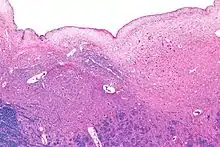

Micrograph of the posterior portion of the open part of the medulla oblongata, showing the fourth ventricle (top of image) and the hypoglossal nucleus (medial - left of image) and the dorsal motor nucleus of the vagus nerve (lateral - right of image). H&E-LFB stain.